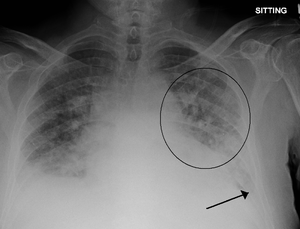

Low oxygen saturation and disturbed arterial blood gas readings support the proposed diagnosis by suggesting a pulmonary shunt. Chest X-ray will show fluid in the alveolar walls, Kerley B lines, increased vascular shadowing in a classical batwing peri-hilum pattern, upper lobe diversion (increased blood flow to the superior parts of the lung), and possibly pleural effusions. In contrast, patchy alveolar infiltrates are more typically associated with noncardiogenic edema[2]